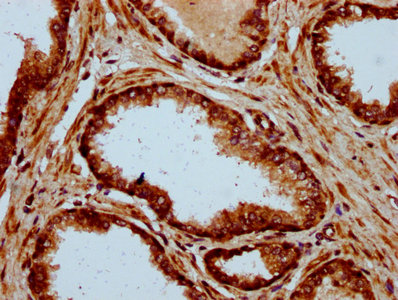

IHC image of CSB-PA891722LA01HU diluted at 1:500 and staining in paraffin-embedded human prostate cancer performed on a Leica BondTM system. After dewaxing and hydration, antigen retrieval was mediated by high pressure in a citrate buffer (pH 6.0). Section was blocked with 10% normal goat serum 30min at RT. Then primary antibody (1% BSA) was incubated at 4°C overnight. The primary is detected by a biotinylated secondary antibody and visualized using an HRP conjugated SP system.